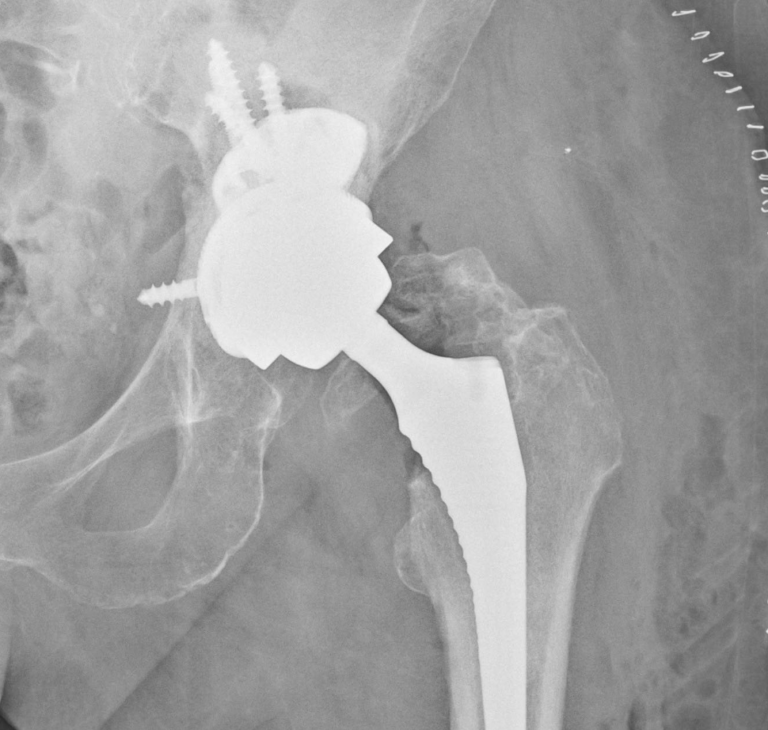

Slovenská medicína zaznamenala historický úspech – lekári z Univerzitnej nemocnice Bratislava sa stali štvrtými na svete a prvými na Slovensku, ktorí použili unikátny revízny modulárny implantát pri operácii bedrového kĺbu.

Zákrok podstúpila 81-ročná pacientka s rozsiahlym kostným defektom v oblasti po implantácii jamky totálnej endoprotézy.

Prednosta II. ortopedicko-traumatologickej kliniky Boris Šteňo vysvetlil, že nový implantát umožňuje kombinovať necementované časti s kostnými štepmi alebo cementom, čo výrazne rozširuje možnosti pri liečbe komplikovaných prípadov.